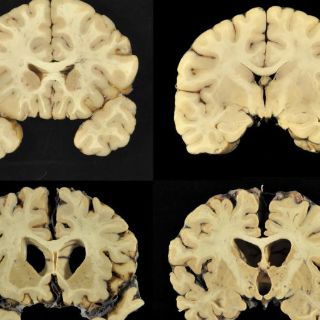

Tras analizar cerebros de algunos fallecidos, detectan encefalopatía traumática crónica

CIUDAD DE MÉXICO (25/JUL/2017).- En un estudio que realizo la neuropatóloga Ann Mckee a cerebros de ex jugadores de la NFL fallecidos, habría encontrado que en 110 de las 111 muestras existía encefalopatía traumática crónica, o CTE, la enfermedad degenerativa que se cree es causada por golpes repetidos a la cabeza.

El CTE tiene como síntomas mareos, incluyendo pérdida de memoria, confusión, depresión y demencia. Los problemas pueden surgir años después del último golpe recibido.